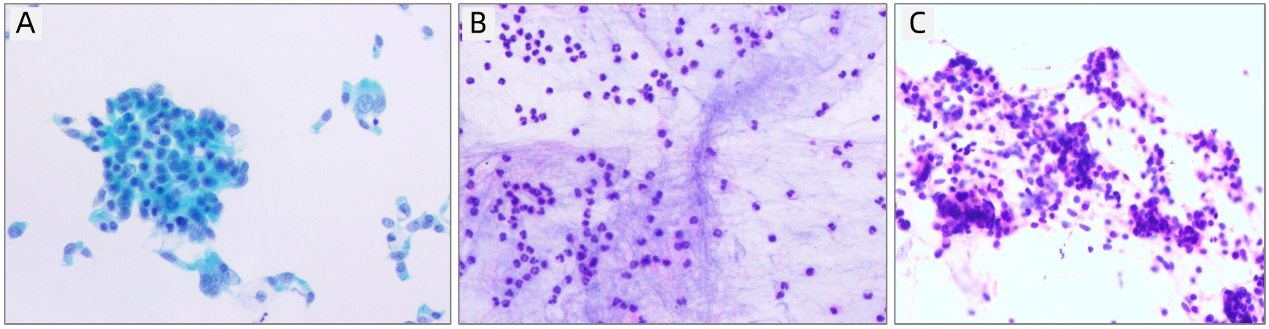

患者,男,64岁,2020-08-19因“胸闷4 d,加重11 h”入院。患者4 d前受凉后出现活动后胸闷、气喘,间断咳嗽、咳痰,于家中自行静脉应用抗感染、舒张支气管、化痰等药物治疗。11 h前误将石蜡油20 mL静脉注射,立即出现持续性胸闷、气喘,剧烈咳嗽,持续约20 min后症状较前稍减轻,至“漯河市中心医院”就诊,给予对症治疗(具体不详),症状无明显减轻,遂来本院。入院查体:体温36.5℃,脉搏86次/min,呼吸20次/min,血压122/80 mmHg(1 mmHg=0.133 kPa),呼吸室内空气氧饱和度88%,左肺吸气相可闻及湿啰音。动脉血气分析(室内静息状态未吸氧):PO2 57.9 mmHg,PCO2 45 mmHg。白细胞13.23×109/L,中性粒细胞10.88×109/L,中性粒细胞百分数82.2%,C反应蛋白16.28 g/L,PCT 0.117 ng/mL。胸部CT(2020-08-19,图 1A)示双肺支气管扩张并感染,左肺为著;双肺胸膜下微小炎性结节考虑。肺动脉CTA,肠系膜动脉CTA及头颅MRA未见动脉栓塞。立即给予吸氧、莫西沙星抗感染、甲强龙抗炎、低分子肝素抗凝、脂肪乳、舒张支气管、化痰等治疗,并分别于入院后16 h、48 h行2次血浆置换。治疗后患者自觉症状减轻,鼻导管吸氧2 L/min,氧饱和度持续 > 94%。入院第3天患者胸闷气喘较前加重,鼻导管吸氧4 L/min,动脉血气分析:PO2 57.8 mmHg,PCO2 58.7 mmHg。给予面罩给氧,增大氧流量,吸氧6 L/min,氧饱和度可维持 > 94%。复查胸部CT(2020-08-25,图 1B)示双上肺絮状高密度影,局部呈磨玻璃样改变。支气管镜示:主气管见大量陈旧性血性粘痰,右上叶、中叶段支气管见大量陈旧性血性分泌物,左上叶可见中等量稀薄分泌物、左下叶段支气管见大量稀薄分泌物。右上叶支气管毛刷涂片细胞学示:镜下见中等量纤毛柱状上皮细胞(图 2A)。右上叶肺泡灌洗液涂片细胞学示:镜下见少量上皮细胞、吞噬细胞及炎细胞(图 2B、图 2C)。肺功能示:重度阻塞性为主的混合型通气功能障碍,肺总量降低,肺活量降低,残气/肺总量%增高,支气管舒张试验阳性。继续给予抗感染、抗炎、抗凝及对症治疗,患者症状逐渐减轻,复查肺部CT较前好转(2020-08-30,图 1C),激素逐渐减量,好转出院。于出院后1个月(2020-09-23,图 1D),3个月(2020-11-17,图 1E)复查胸部CT,双肺病灶逐渐好转,随访1年,患者恢复良好。

| A:右上叶支气管刷检(巴氏× 400);B、C:右上叶肺泡灌洗液涂片(HE× 400) 图 2 患者细胞学染色图 |

既往有病例报道称静脉注射油类物质所致肺炎为脂质性肺炎,肺泡灌洗液中可见泡沫状、富含脂质的肺泡巨噬细胞[1]。脂质性肺炎报道更多见于吸入油类物质所致的肺部病变。本病例行气管镜肺泡灌洗液细胞学检查见少量上皮细胞、吞噬细胞及炎细胞,与脂质性肺炎的细胞学表现并不相符。可见,静脉注射油类物质所致的肺部病变并不一定是脂质性肺炎,其病理生理机制异于吸入油类物质,与脂肪栓塞综合征更为类似。1974年Hausberger等[3]用矿物油对实验大鼠进行股静脉注射模拟脂肪栓塞综合征模型,结果显示注射矿物油后,肺组织病理学改变主要包括血管周围水肿、出血和浸润;肺泡间隙和小支气管出血;肺泡细胞的分解和死亡,这些变化在注射后第1天明显,第3、4天达高峰,第9天水肿减轻,出血浸润仍明显,第20天,大面积的肺表现正常,与本病例病程相似。目前脂肪栓塞综合征导致肺功能障碍的机制存在两种理论[1]:一为生化理论,油脂沉积于肺毛细血管刺激局部炎症因子释放,血管内皮受损,血管通透性增加,油脂渗透入肺泡内导致肺泡内渗出出血,受损的肺血管内皮细胞可触发促炎细胞因子级联反应。另外油类物质对肺实质细胞、毛细血管内皮细胞及肺泡表面活性物质有直接毒性作用。二为机械理论,油脂进入静脉后随血液循环阻塞肺毛细血管,导致通气血流比例下降。但本病例肺动脉CTA并未发现肺动脉阻塞征象,考虑可能因为油类物质CT下不显影、油脂小分子沉积于肺毛细血管并未阻塞肺大血管或油类物质进入肺血管后引起血管反应性痉挛并未完全堵塞血管。